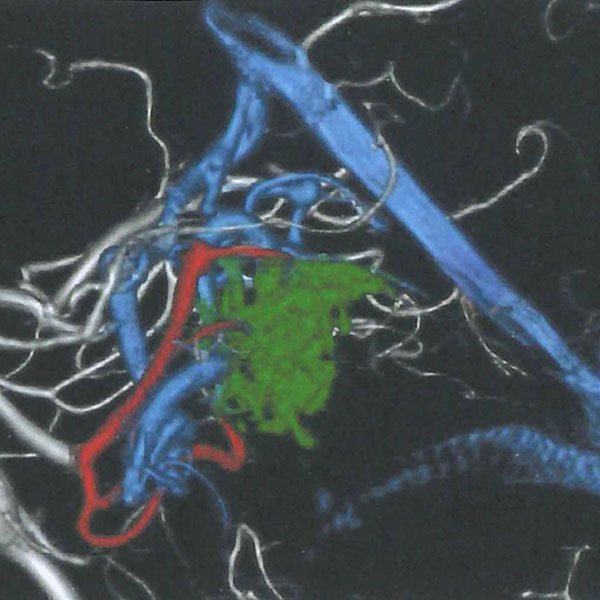

脳血管撮影

手術前

手術後

手術中